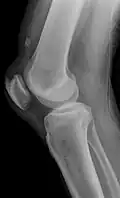

| An x-ray demonstrating quadriceps tendon rupture. Note the abnormal angle of the patella and soft-tissue swelling marked by the arrow. | |

A quadriceps tendon rupture is a tear of the tendon that runs from the quadriceps muscle to the top of the knee cap.[1]